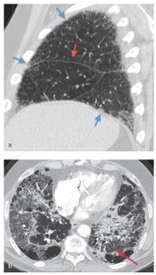

此时尽管骨折部位仍然肿胀,但其在压力下不再柔软或活动,通常认为骨折愈合了。放射学上,与原始管状板层骨有明显的区别,管状板层骨仍然明显破碎,但在伤口周围由编织骨的袖带连接,在X线片上表现为松散的骨网(图2)。

图2 骨折的自然演变(红色箭头)

几个因素影响骨折愈合的速度,尤其是骨折的类型和位置(上肢比下肢骨折愈合快,斜或螺旋骨折比横向骨折愈合更快)。年龄和病人的营养状态,如一个孩子肱骨螺旋骨折可能3周的时间就能愈合,而一位上了年纪的病人、一个成年人和一个粉碎性骨折患者骨折愈合可能需要24周的时间。

编织骨需要几周或几个月的时间才能被骨内的破骨细胞重塑,成骨细胞则需要沿着压力线形成板层骨。一旦愈合,患者能够承受重量,肿块状的新皮质骨逐渐被吸收,多余的髓质新骨被移除,恢复正常的髓腔。编织骨被完全吸收并被板层骨所取代,恢复正常可能需要长达一年的时间。